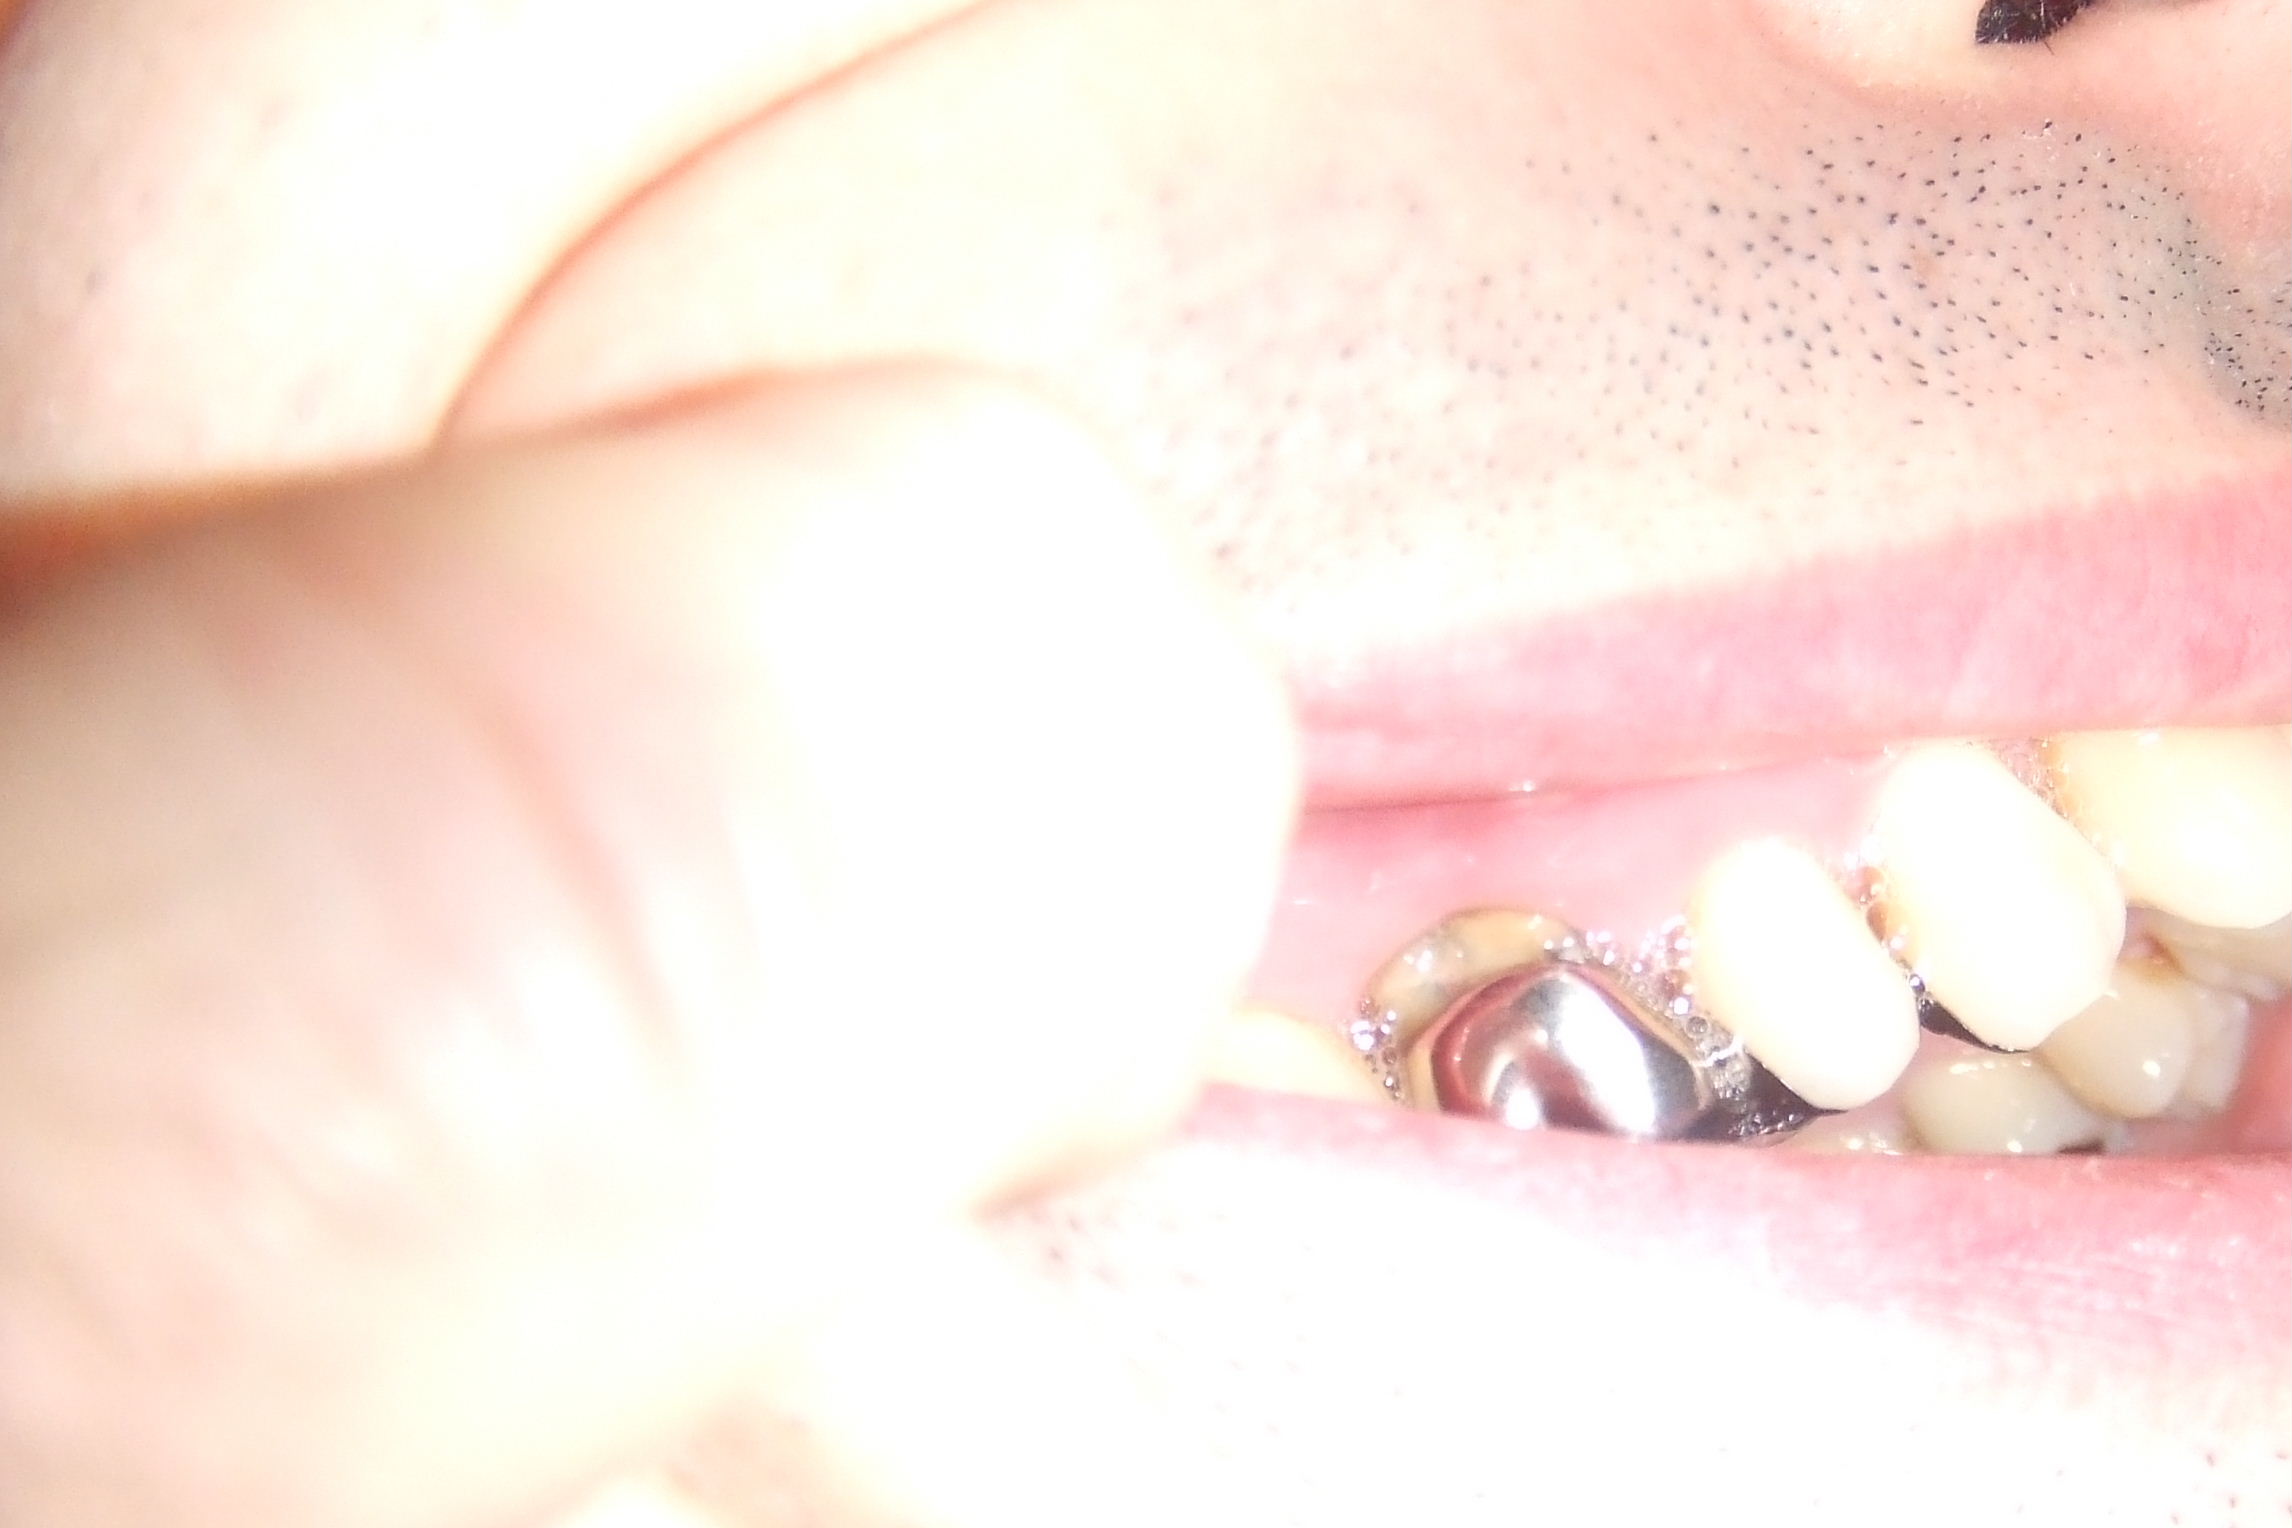

画像2

同じ歯をCTで上から見たところです。

左側の歯は根っこがパックリ割れている事が確認できます。

そして、周囲の骨が溶けて無くなっているのが解ります。

右側の歯は2本の根っこの中に神経管(根管)が4つあることがわかります。

そのうち1本の根管にはお薬が詰まっていない事がわかります(白い丸がお薬です)。

このように3次元的に見る事で平面的なレントゲンでは解らなかった事がCTでは(素人さんでも)解るようになるのです。

この画像診断から‥

7番は残念ながら抜歯。

6番はお薬の入っていない根っこを治療すれば良い。

と言う治療計画が立てられます。

もちろん、診断能力に優れたドクターであれば平面のレントゲンだけでも判断はできるのですが‥。